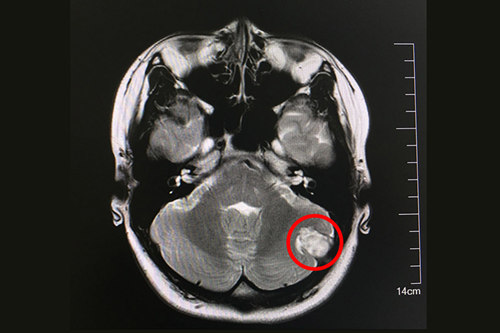

在藍十字腦科醫(yī)院做了核磁共振等一系列檢查之后,侯增欣主任及影像科孫海輝主任等對靜靜的病情做了討論,大家提出種種猜測:腦膜瘤?顱骨腫瘤?黃色素瘤?腦膿腫物? 但最后都否定了。唯一不可否認的是,這個病變現(xiàn)在已經(jīng)從頭皮侵入患者小腦,如果不加干預,以后會越長越大,到時將嚴重影響患者的小腦功能,甚至威脅生命。最后,各位專家一致認為:盡快做手術才是良策。

術前核磁顯示:左側(cè)后顱窩實性腦外占位病變,與左枕骨寬基相連